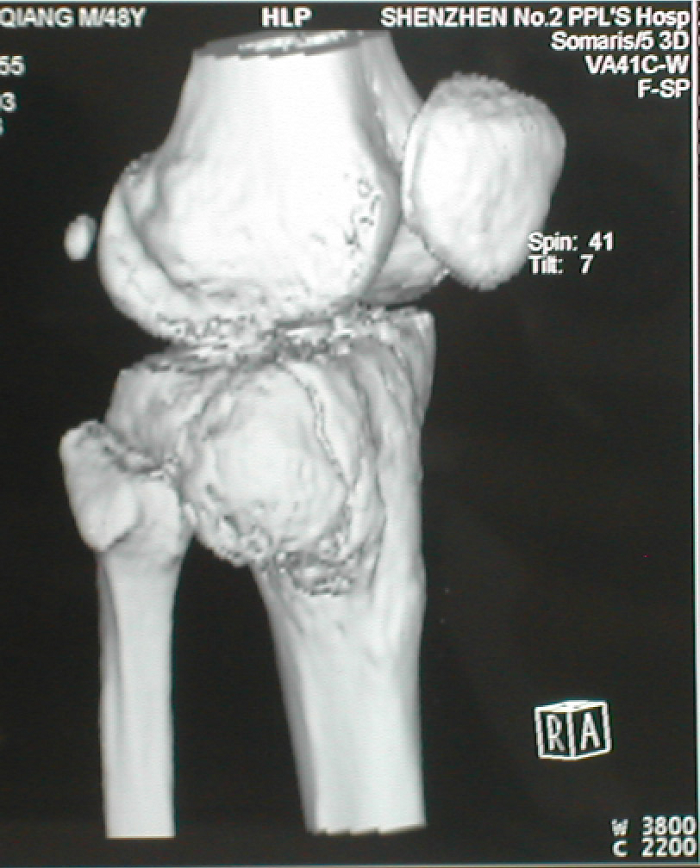

3.病例3:男 48岁, 右胫骨近端骨巨细胞瘤(Campanacci Ⅲ级),行瘤段广泛切除异体半关节移植术

图 9 术前X线片

图 10、11 术前CT